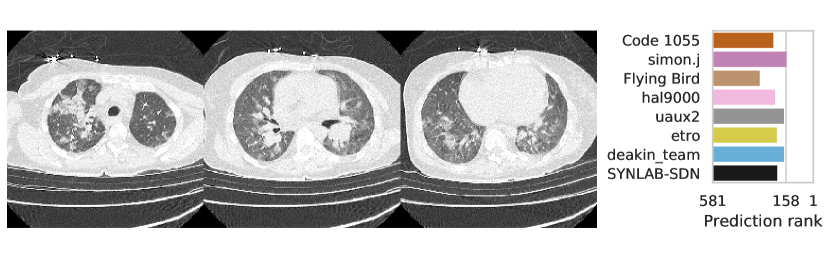

3.2.3 Performance

Table 1 shows the AUC on test set B for COVID-19 presence and severity of the teams that submitted to the Final phase. Figure 4 shows Receiving Operating Characteristics (ROC) curves of the six successful Final phase submissions for discriminating between severe and non-severe COVID-19 subjects from test set B. Figures 5 and 6 show how the finalists ranked the subjects from test set B with severe and non-severe COVID-19 respectively for presence of severe COVID-19. Figures 7 and 8 highlight some individual cases from test set B. During the original STOIC project [67], a logistic regression model was developed to predict severe COVID-19 using clinical variables and CT annotations by radiologists. It was developed and evaluated using the patients from the STOIC who were COVID-19 positive for both RT-PCR and CT, and had unenhanced CT. Of these 4238 patients, 1000 developed severe COVID-19. Revel and colleagues 6 reported an AUC for this model of 0.69 (CI: 0.67-0.71). To compare this model against the results from STOIC2021, an ensemble of the top three solutions for severe COVID-19 prediction was evaluated on the 367 patients from test set B who were COVID-19 positive for both RT-PCR and CT, and had unenhanced CT. 97 of these patients developed severe COVID-19. The top three ensemble achieved an AUC of 0.783 (CI: 0.706-0.848).